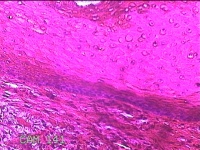

左侧肘后包块

性别

男

年龄

58岁

临床诊断

皮下结节

一般病史

发现左侧肘后包块半个月余,无明显疼痛及不适。

标本名称

大体所见

灰白暗红色带皮肤样包块1.5x1.3x0.3cm一个,表面糜烂,切开包块呈实性,切面灰白暗红色,质软。